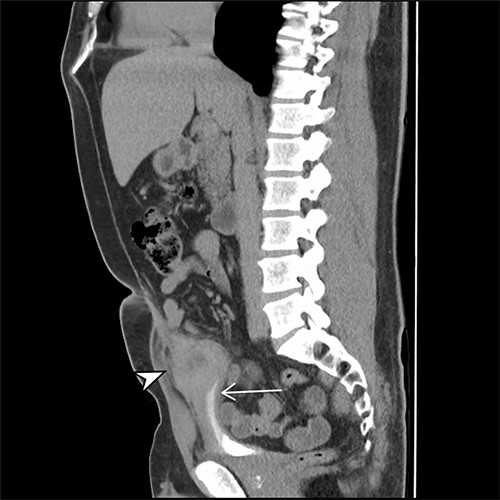

A 41-year-old, previously well, male presented to the emergency department with lower abdominal pain, pyrexia with a temperature of 38.2°C and a palpable suprapubic mass. His relevant background history included an uneventful laparoscopic appendicectomy 2 years prior for acute appendicitis, insulin independent type 2 diabetes and hypertension. He presented with raised inflammatory markers and computed tomography (CT) showing a well circumscribed central pelvis lesion that appeared concerning for a urachal malignancy (Fig. 1). This lesion was closely associated with the dome of the bladder (Fig. 2). This supracystic lesion measured 58 mm × 56 mm with central cystic component of 15 mm in diameter, and contained a 11 mm central calcification. Further characterization with magnetic resonance imaging showed possible extension of this mass to the rectus abdominis without significant lymphadenopathy (Fig. 3). Flexible cystoscopy only found inflammation at the dome. As urachal malignancy could not be unequivocally excluded on imaging studies alone, following multidisciplinary discussion, the decision was made to perform an excision of this lesion.

Sagittal CT cystogram. Arrowhead indicates involvement of anterior abdominal wall. Arrow indicates association of lesion with the dome of the bladder.